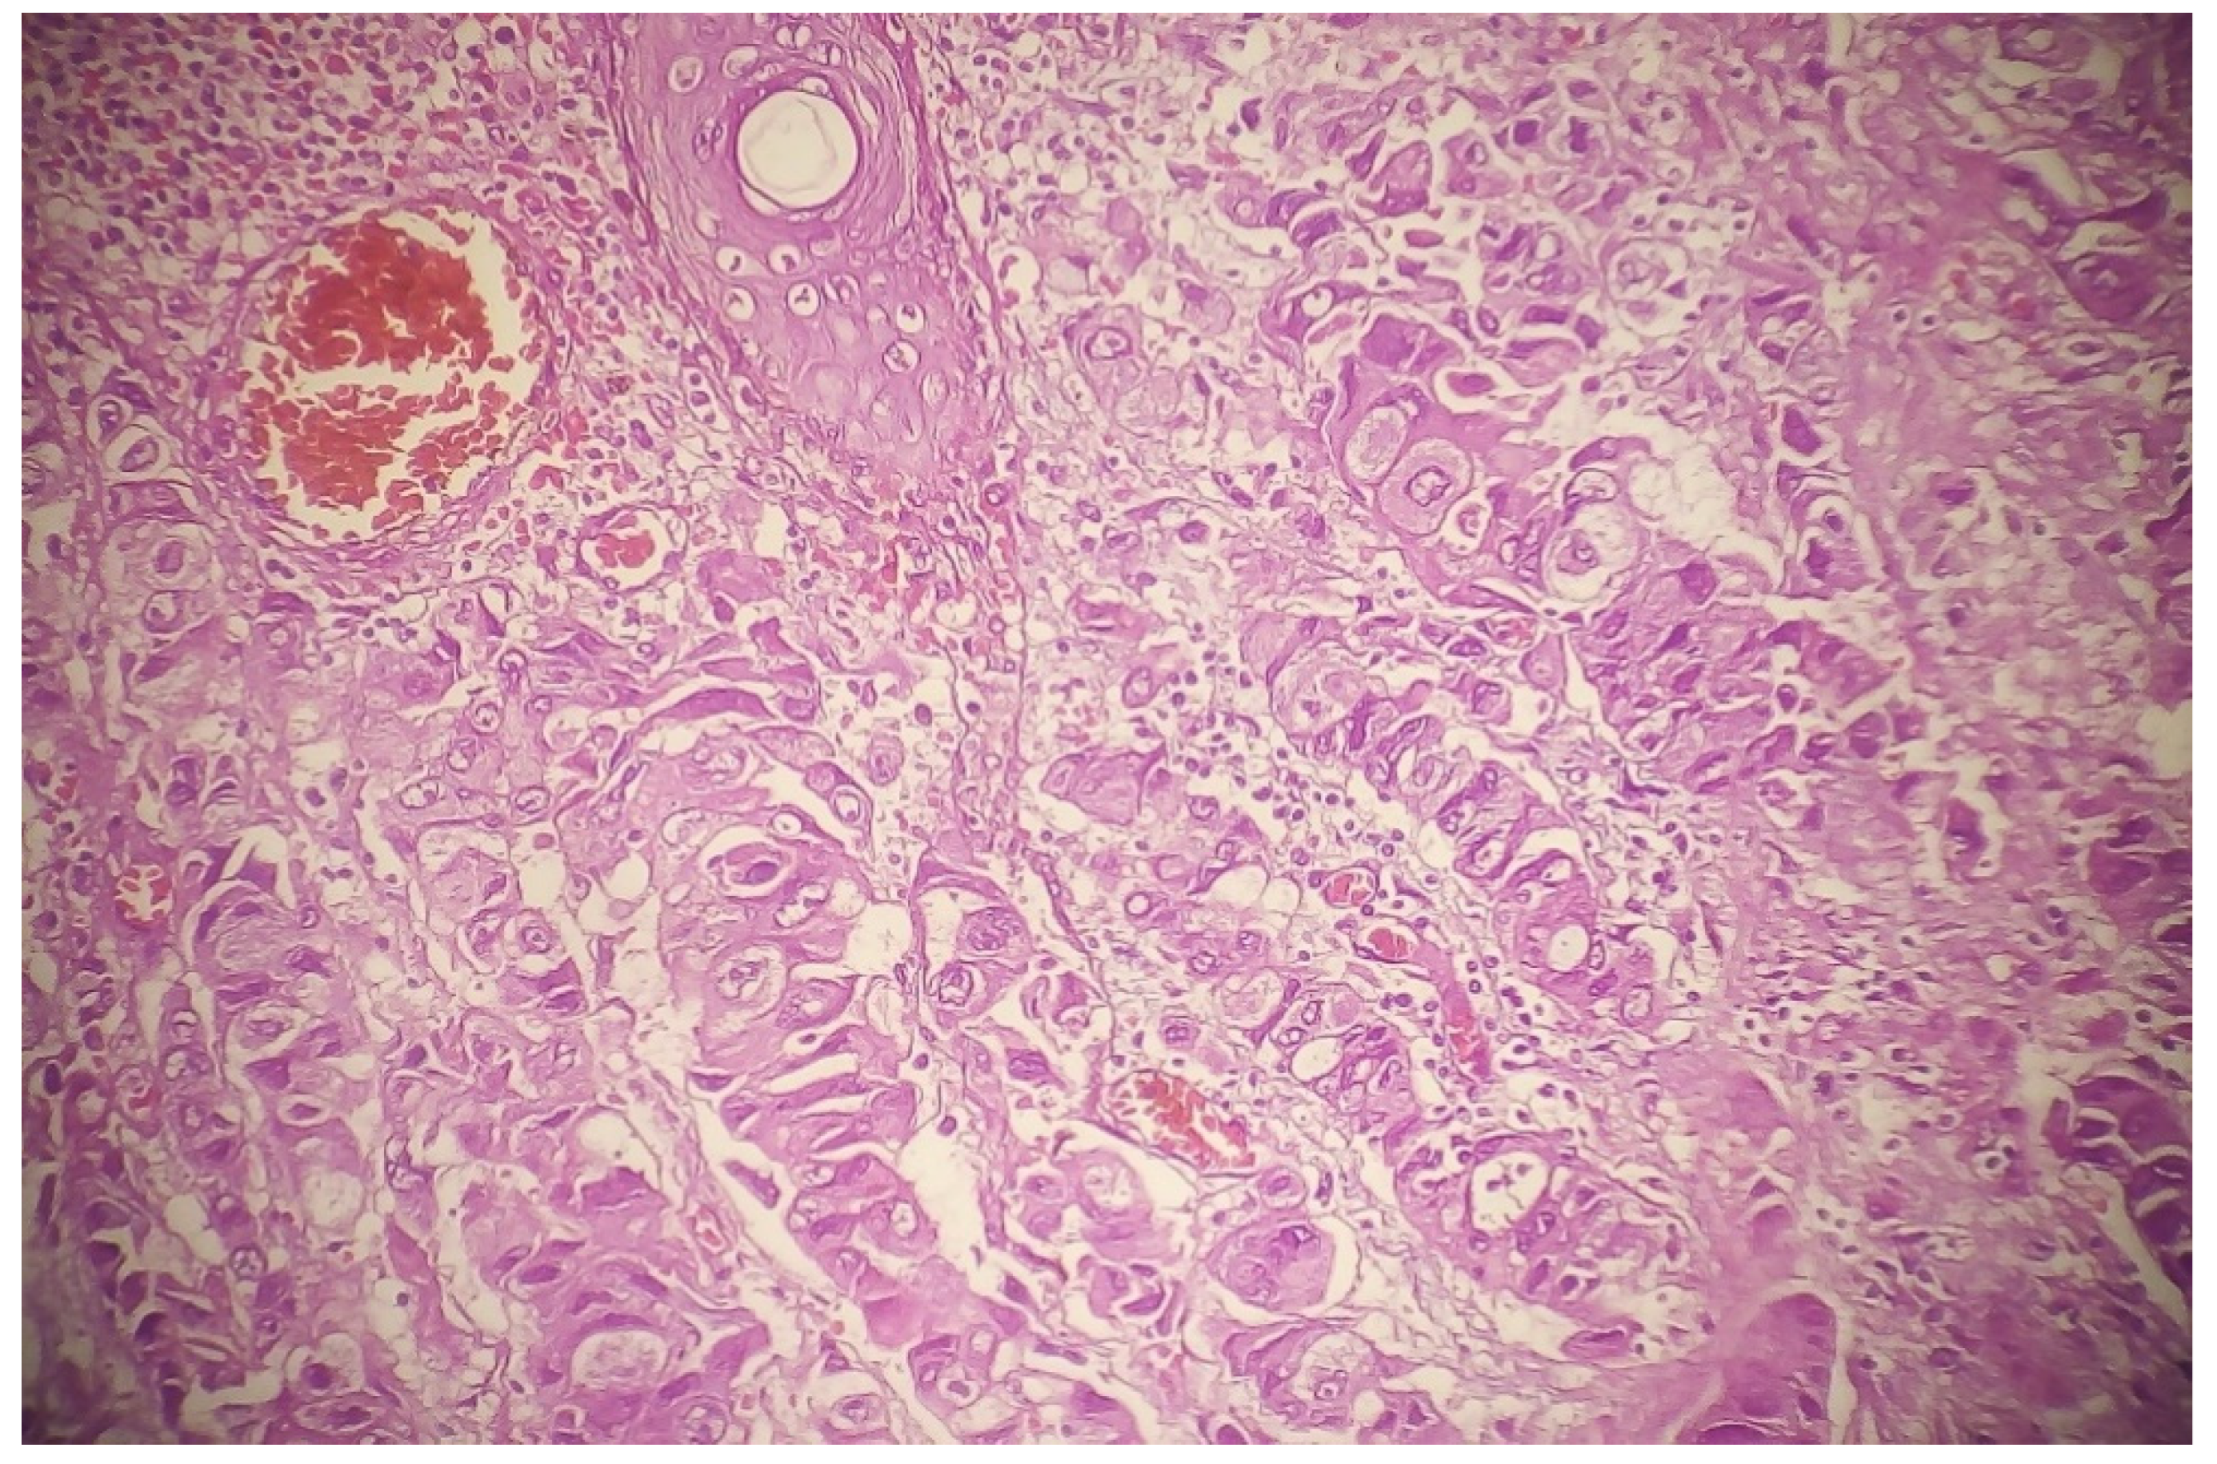

We retrieved the genetic data corresponding to 13 cases of ASCs and 15 cases of MACs of minor salivary glands. The histologic features of ASCs and MAC are shown in Figure 1. Figure 2 shows the genetic analysis of ASCs. What characterized the genetic profile are mutations in BCOR, CDH1, CEP57, ERCC4, GEN1, KLF4, LAMA5, MAC, MET, MN1, MTOR, NF2, PCLO, PRDM1, RB1, RELN, RIK3R1, SMARCB1, SOS1, and TP53 genes. Figure 3 shows the genetic network analysis for the possible interrelations between these genes. Cases of MACs showed mutations in AKT1. Regarding the immunohistochemical profile of ASCs, the squamous component stains with p63, p40, and cytokeratin 5/6.

3.2. Morphologic Difference in Different Sites

Most of the reported ASCs contained dense squamous congregations intermingled with true duct structures that showed cellular atypia. The stromal adenocarcinomatous component must be neither too superficial and inconspicuous (so as not to be considered an adenoid squamous cell carcinoma) nor very deep (so as not to be considered invasive SCC) (Figure 2). These cases are always considered high-grade. MACs are considered ASCs without an overlying SCC. For example, adnocarcinomatous lesions that secrete mucin and do not align with a particular recognized morphology (e.g., HG-MEC or high-grade mucinous cystadenomacinoma) are considered MACs. The indicated diagnostic immunohistochemical panel is rarely investigated. Figure 4 compares a case of MACs with a high-grade MEC of the minor salivary gland. Figure 5 shows a case of low-grade MAC of the lung. On the other hand, the ASCs of breast show both low-grade and high-grade features (Figure 6).

Figure 2. ASC of minor salivary gland.